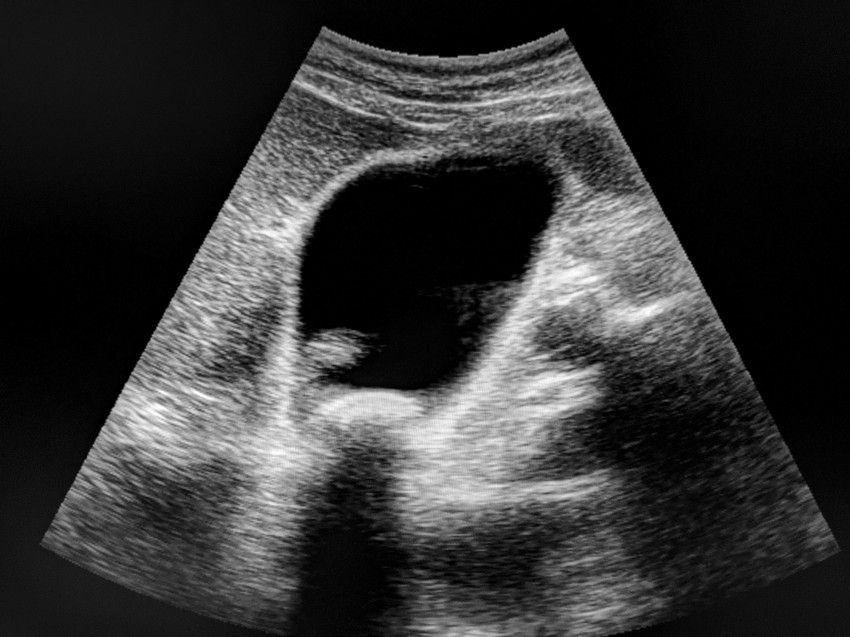

Epekő gyanúja esetén elsődlegesen képalkató vizsgálati eljárásokat alkalmaznak, így pl. ultrahangot, röntgent, ritkábban CT-t vagy MRI-t (ezek azonban csak bizonyos típusú köveket képesek kimutatni). Az ultrahangos vizsgálat során már akár 2 mm-es köveket is észlelni lehet, és ezzel a vizsgálattal az epehólyag ürülési funkcióját is ellenőrizni lehet.

Epekövesség gyanúja esetén és általában minden hasfájással járó tünet esetében érdemes hasi ultrahangvizsgálatot végezni.